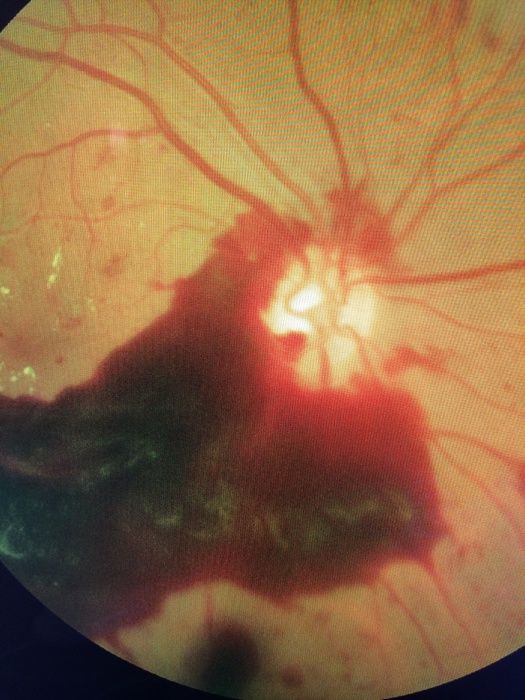

Während die in Teil 1 besprochenen krankhaften Veränderungen innerhalb der Netzhaut zu finden sind (nicht proliferative Retinopathie), zeigt sich im nächsten Stadium eine Neubildung von feinsten arteriellen Blutgefäßen in den Glaskörperraum, den sogenannten Proliferationen. Bei diesem Krankheitsbild wird nun von der stark sehkraftgefährdenden proliferativen Retinopathie gesprochen.

Die neu gewachsenen Blutgefäße bilden sich bei Sauerstoffmangel in diesem Netzhautgebiet. Diese feinen und dünnen Gefäße sind jedoch in ihrem Zellaufbau bei weitem nicht so stabil wie die normalen, angeborenen Arterien. Unter Druckbelastung, wie erhöhtem Blutdruck, starkem Husten, Pressen beim Stuhlgang, bei körperlichem Arbeitsstress und ähnlichem können diese minderwertigen kleinen Gefäße aufreißen. Es blutet hierdurch in den Glaskörperbereich mit der Folge, das innerhalb von wenigen Sekunden die Sehkraft sehr stark oder auch völlig verloren geht. Jetzt ist nach einer augenärztlichen Untersuchung meistens viel Geduld vom Patienten gefordert.

Die Glaskörperblutung resorbiert sich häufig wieder. Dies ist ein zeitlich längerer Prozess, der auf osmotischem Prinzip beruht. Wenn nach Abwarten von etwa vier bis sechs Wochen die Sehkraft jedoch nicht wieder zurückgekehrt ist, dann wird eine sogenannte Vitrektomie notwendig. Dies ist ein operativer Austausch des eingebluteten Glaskörpers gegen klares Silikonöl. Damit gewinnt der Patient diejenige Sehkraft zurück, die vor der Glaskörpereinblutung bestand. Es erlaubt nun auch dem Augenarzt wieder den Einblick auf die Netzhaut. Häufig wird nun zur Vermeidung einer neuen Einblutung eine Lasertherapie der Netzhaut notwendig, wenn noch proliferative Gefäßwucherungen oder andere therapienotwendige Veränderungen vorliegen.